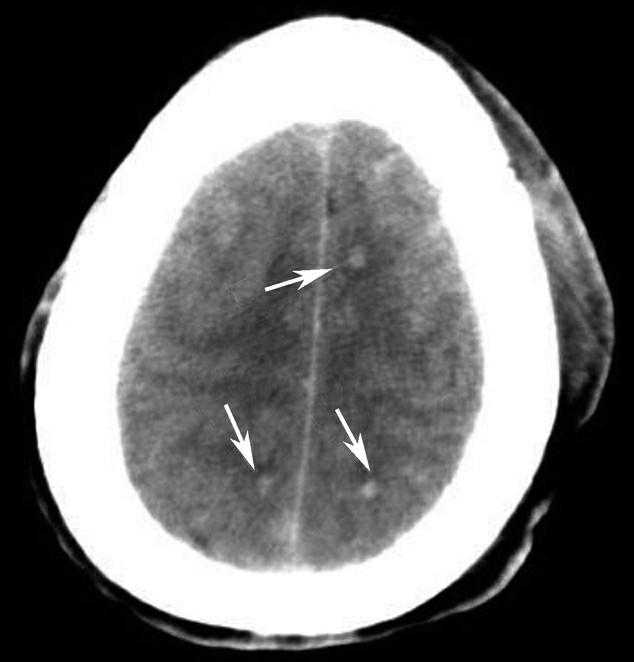

图1-2-28 苍白球生理性钙化

A.双侧苍白球对称性钙化,呈高密度影(箭);B.左侧苍白球钙化(箭),右侧苍白球钙化不明显